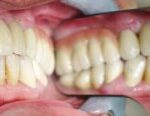

Vorher: Alte Implantat-Krone kleinerer Schneidezahn ; nicht ansprechende Ästhetik Frontzähne

Nachher